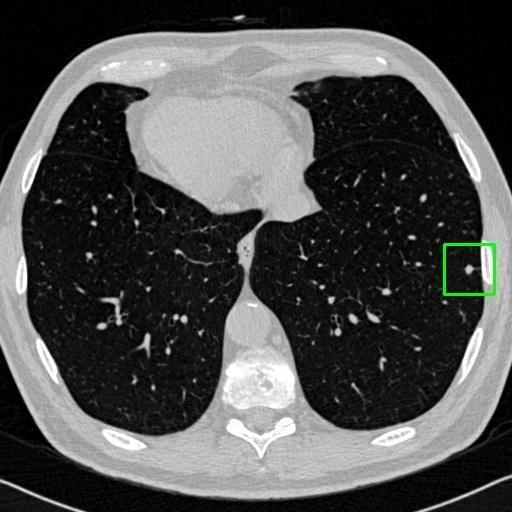

We developed an AI-based system using deep learning models for analyzing lung CT scans to detect and classify pulmonary nodules. We chose the YOLOv11 architecture for its enhanced object detection capability and adapted it specifically for medical imaging, incorporating pixel-level precision and severity classification.

Classification into three severity levels with colored bounding boxes.

Maintaining performance on small, complex features like micro-nodules tested the limits of traditional object detectors.

Successfully built and deployed an AI model (YOLOv11) capable of detecting lung nodules in CT scans with high accuracy and real-time performance.

Designed a severity classification system that categorizes nodules into null, moderate, and severe using colored bounding boxes, assisting in rapid clinical decision-making.